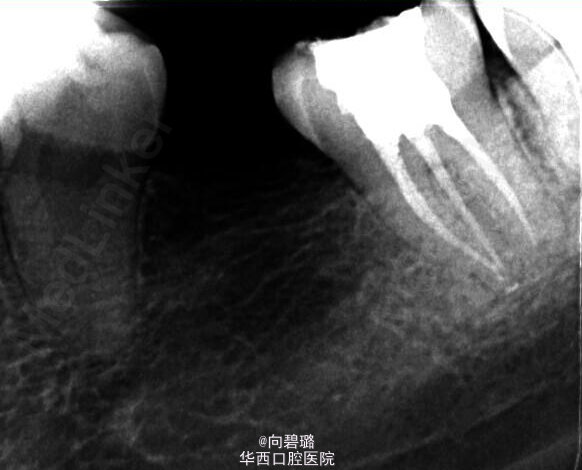

37牙根管预备过程中,由于其近中根疏通不畅,照片,牙胶失踪疑似底穿,加大投照角度依然如此。那么我们在临床工作中应该怎么样辨别底穿与否?首先X片是一个很直观的图像,一般来说可以从X片上看出来底穿与否(牙槽中隔是否有破坏或炎症性吸收),但是遇到磨牙三个根,四个根的情况时,由于投照角度的问题可能会不太好辨别,这个时候可以扩大探针看是否有出血,病人是否感觉疼痛,这都是一些辨别的手段。(来自:http://blog.kq88.com/88868.html)